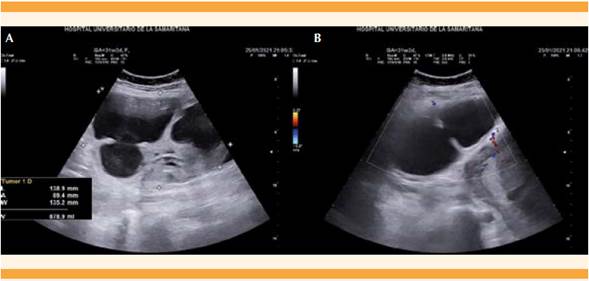

Paciente de 34 años, con antecedentes obstétricos de cuatro embarazos: dos partos y dos abortos, con 31 semanas de embarazo al ingreso al Hospital Universitario de la Samaritana de Colombia, justificado por un cuadro clínico de 18 horas de evolución consistente en: dolor abdominal intenso, tipo punzada, de predominio en la fosa iliaca y el flanco derechos. Durante el examen físico, con signo de Blumberg positivo y signos de irritación peritoneal, altura uterina de 30 cm y feto único vivo cefálico, con bienestar fetal por cardiotocografía reactiva, sin actividad uterina. La ecografía obstétrica documentó que se trataba de un embarazo de 31 semanas, con feto único vivo y gran masa anexial derecha, de características complejas, multitabicada, con dimensiones de 138 x 89 x 135 milímetros para un volumen de 878 cm3. Debido al cuadro clínico y los hallazgos ecográficos se consideró que se trataba de un episodio de abdomen agudo con torsión anexial. Ante este panorama se decidió la laparotomía de urgencia. Los hallazgos intraoperatorios fueron: várices pélvicas, hemoperitoneo de 100 cc, masa dependiente del ovario derecho, torcida, de 15 x 15 centímetros, aproximadamente, con signos de sufrimiento, necrosis y ruptura en torno de su pedículo. La trompa derecha se reportó macroscópicamente sana. Figuras 2Ay2B

Figura 1 A. Ecografía abdominal: muestra un quiste complejo de 138 x 89 x 135 mm para un volumen de 878 cc. B. Captación al Doppler.